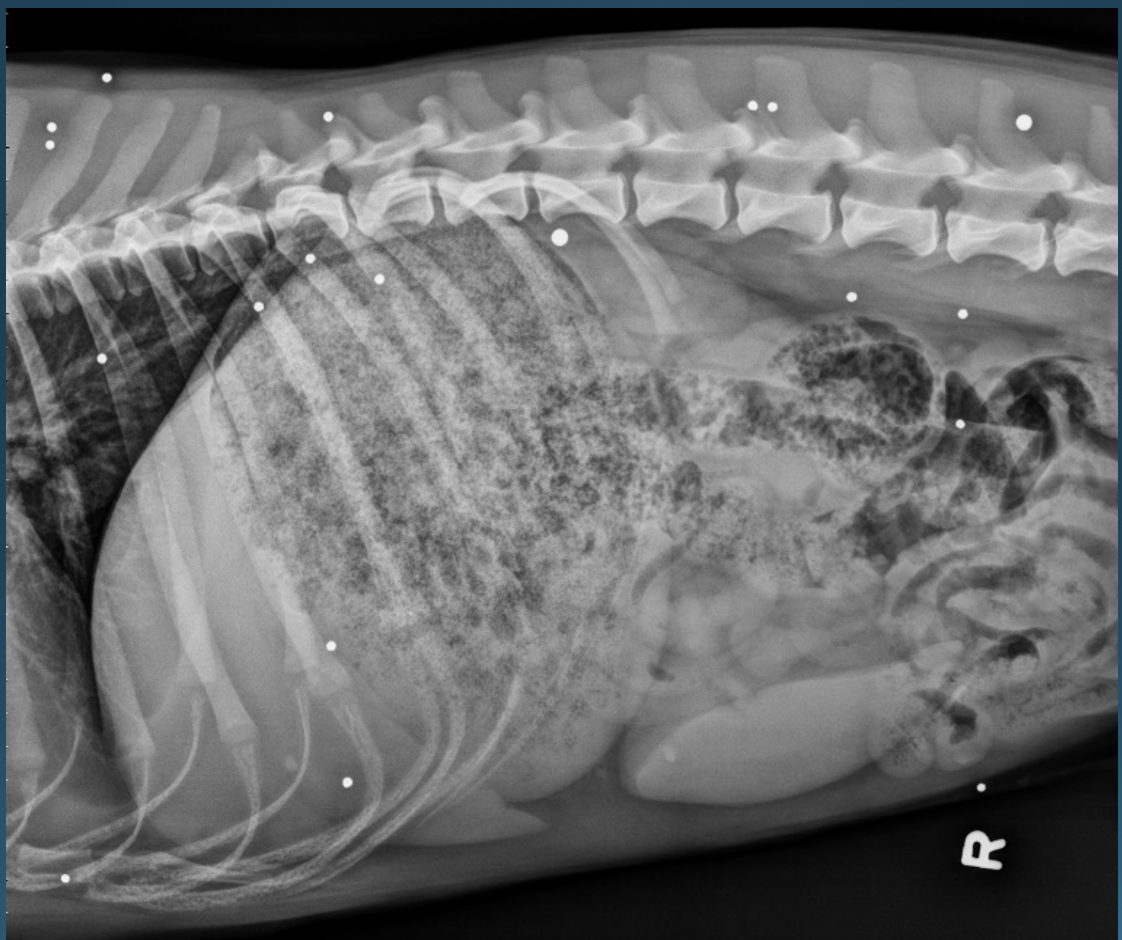

What is shown in this image?

A

normal right lateral view in the dog